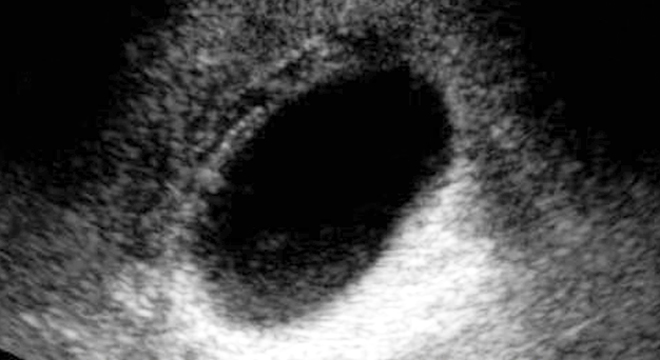

- Ultraschall: Damit lassen sich vorhandene Steine nachweisen